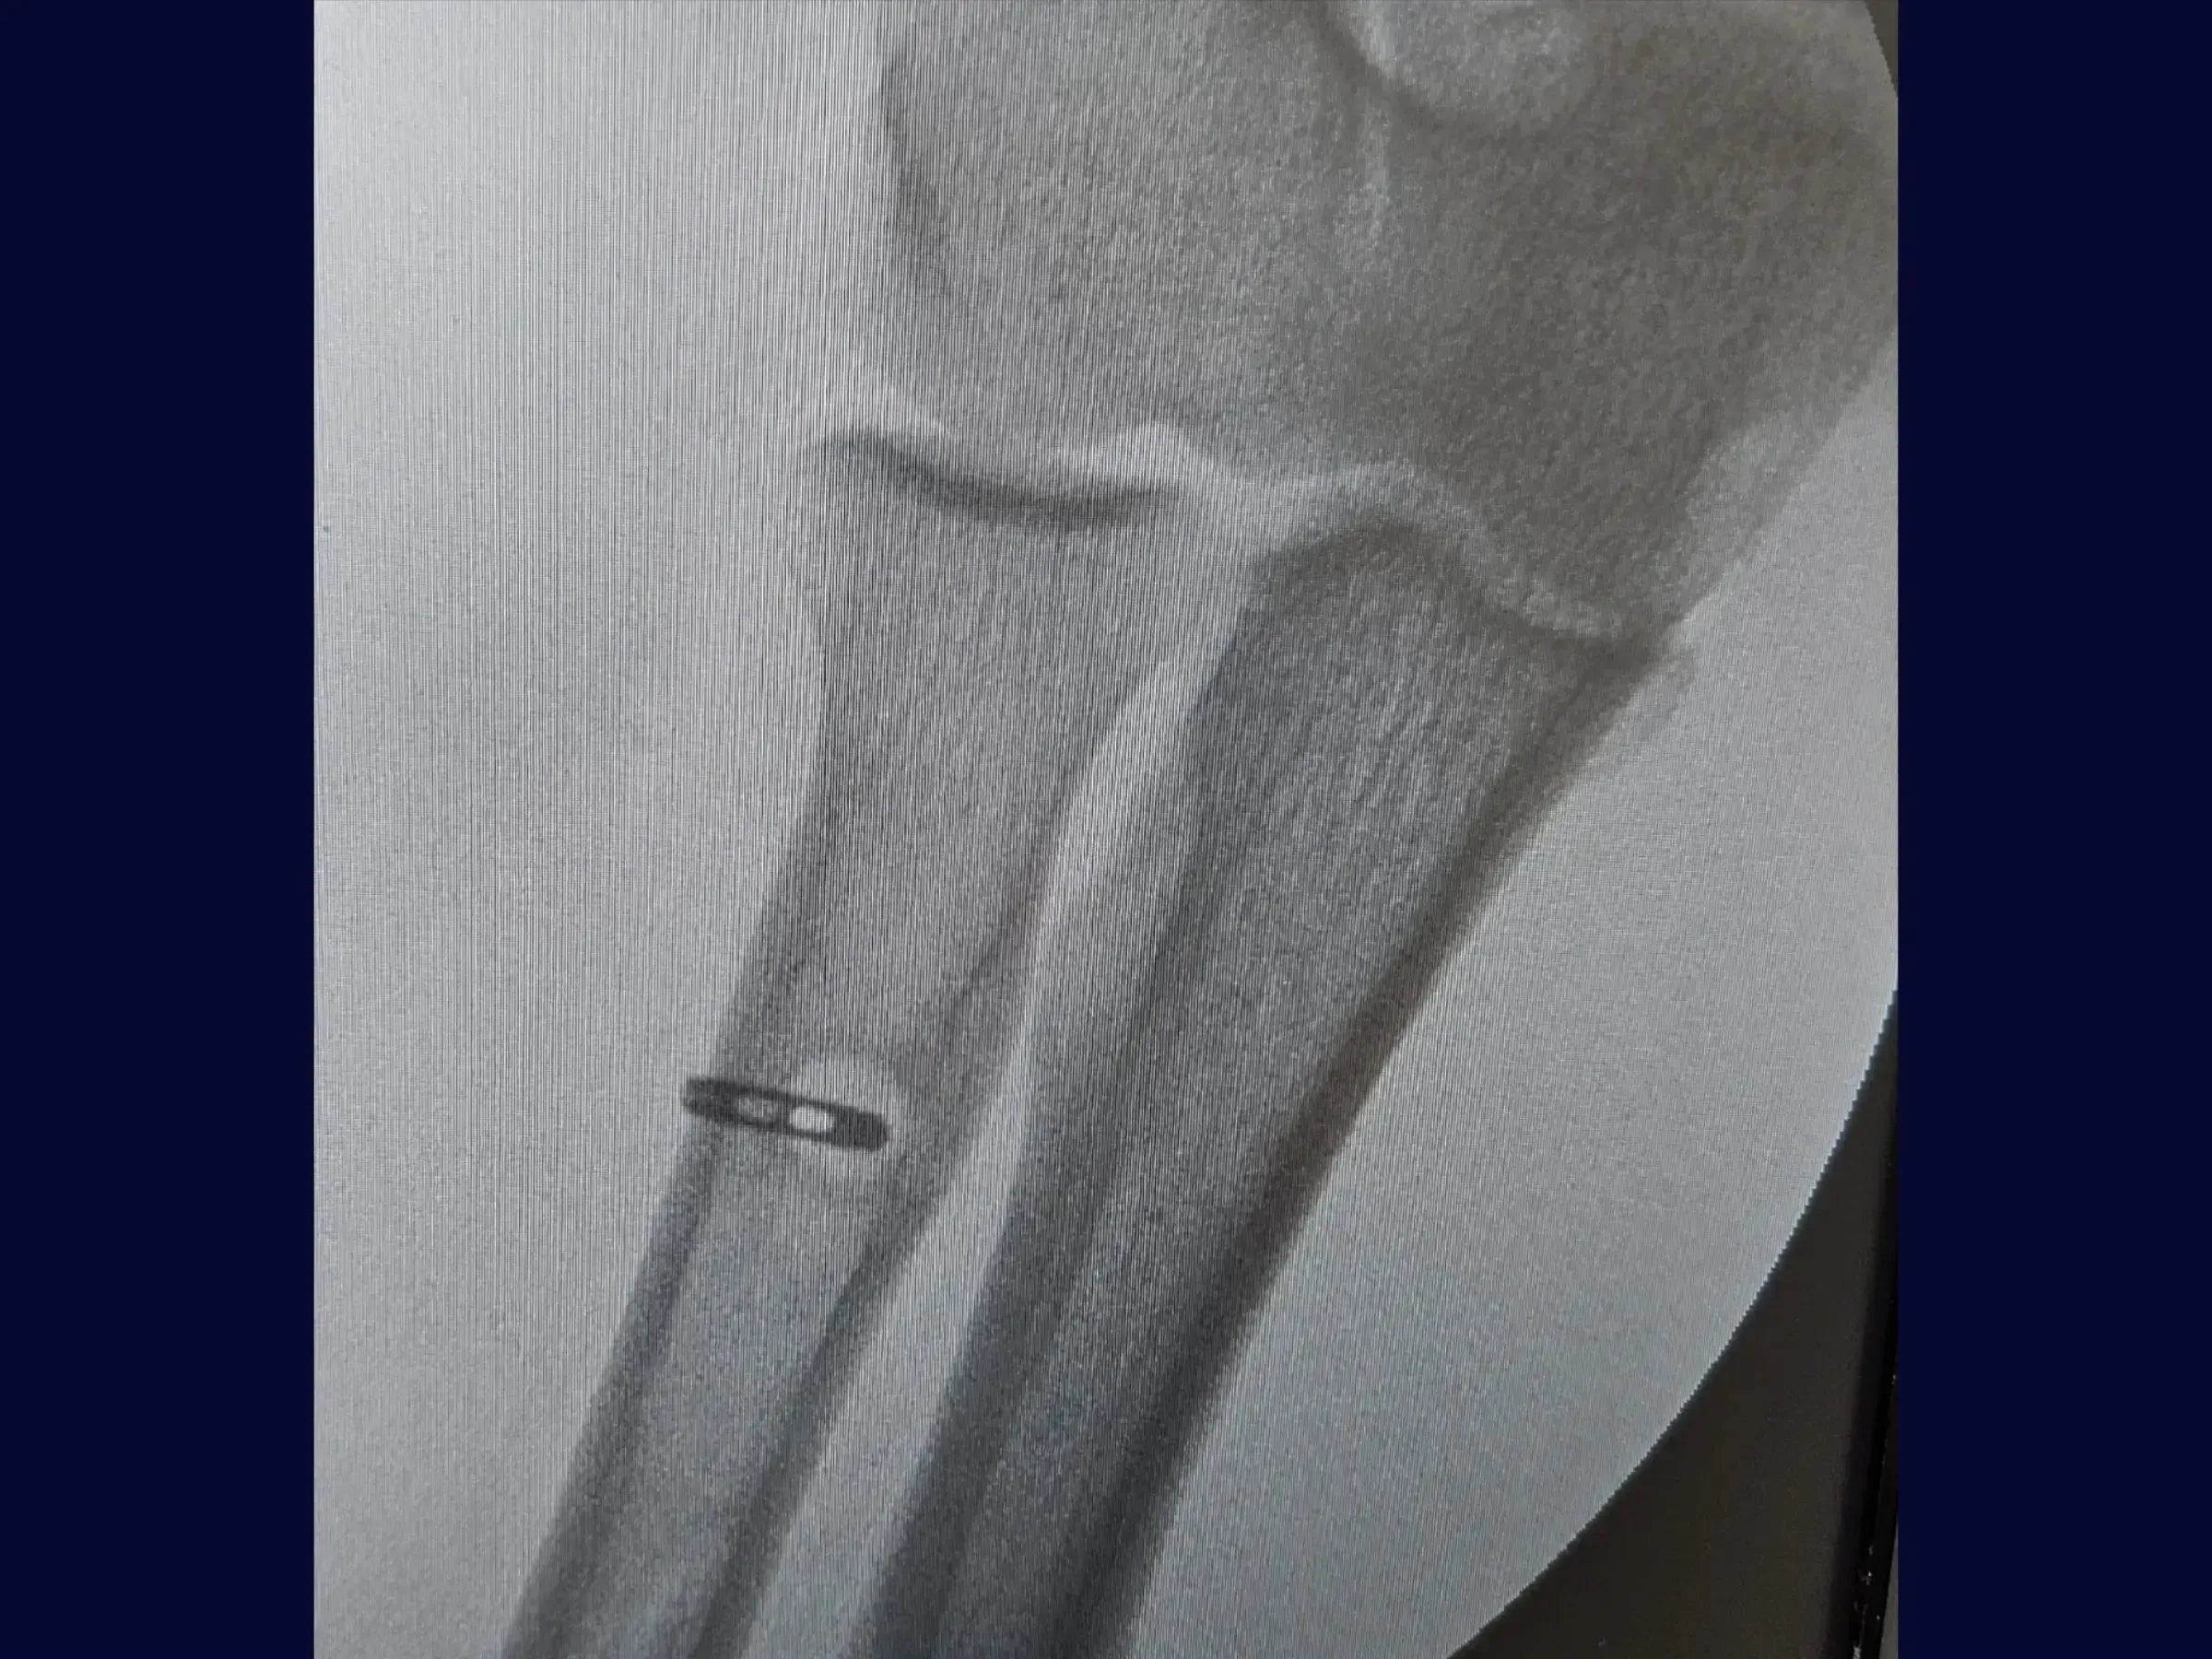

- Orifício Ósseo e Fixação: Medição da espessura tendínea, perfuração das corticais com fio guia e broca, criando orifício de 7 mm na primeira cortical.

- Reinserção com TightRope: Introdução e fixação do tendão já suturado com o dispositivo TightRope no lado oposto do rádio.

- Verificação e Fechamento: Radiografia confirma o orifício. Acesso anatômico e delicado, sem lesões musculares, com resultado estético favorável.